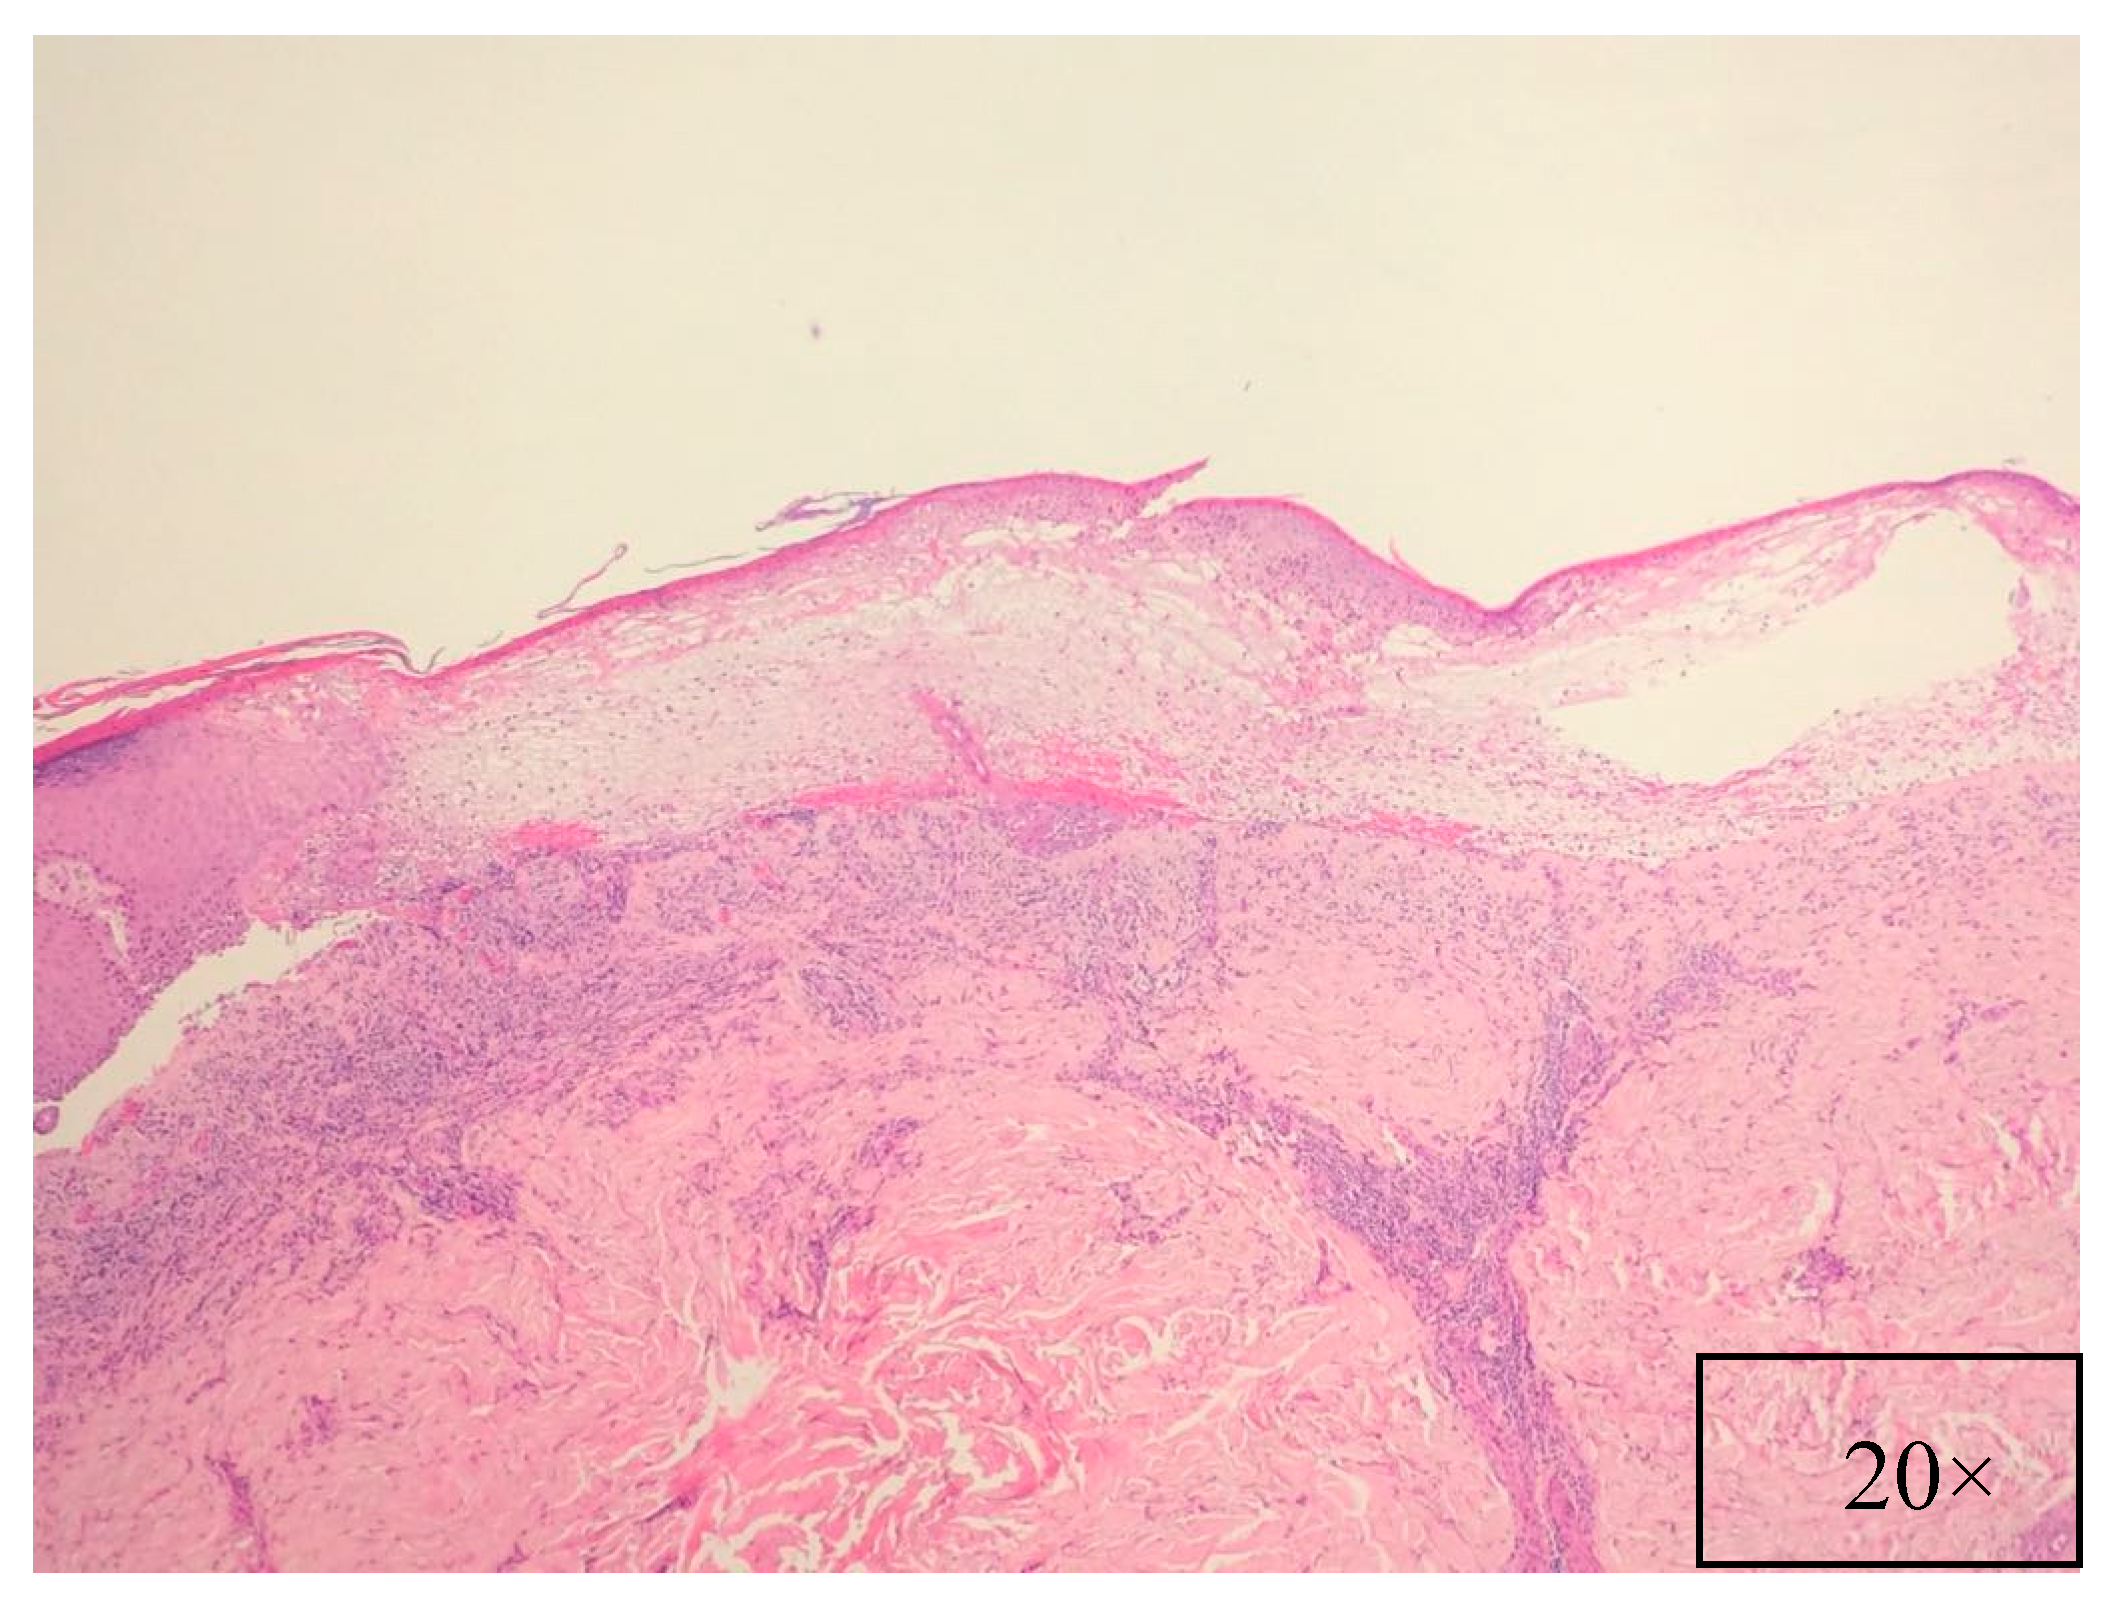

7. Pathology

| Histopathology | Suprabasal intraepithelial acantholysis, vacuolar interface changes, necrosis of individual keratinocytes, and/or lichenoid inflammation |